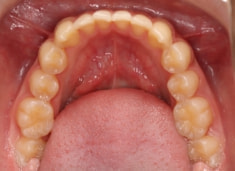

治療前

上下顎のギャップはありますが、顔面自体の幅径は良好な値を示していますので、スペース不足は拡大することによって解決できポテンシャルはあると考えられます。

左右の非対称もさほど強くありません。